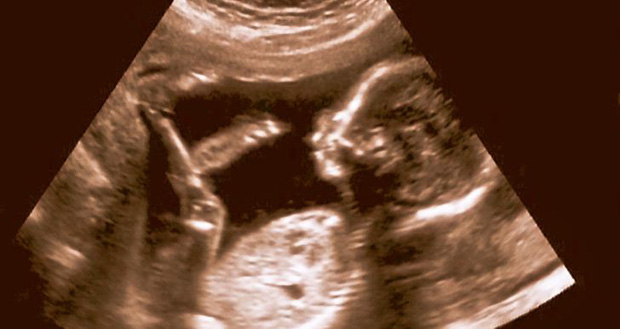

3. Dần dần, sinh con tự nhiên sẽ trở thành không thể

Sinh mổ là một giải pháp sinh nở được áp dụng rất nhiều ngày nay, do khả năng giảm thiểu rủi ro trong trường hợp thai nhi quá lớn so với xương chậu của mẹ. Tuy nhiên, việc ngày càng nhiều bé gái ra đời bằng cách này cũng vô tình khiến nhiều phụ nữ cần sinh mổ hơn sau này.

Theo các nhà khoa học, đây là một hệ quả của quá trình tiến hóa, và dần dần chuyện sinh tự nhiên có thể biến mất trong tương lai.